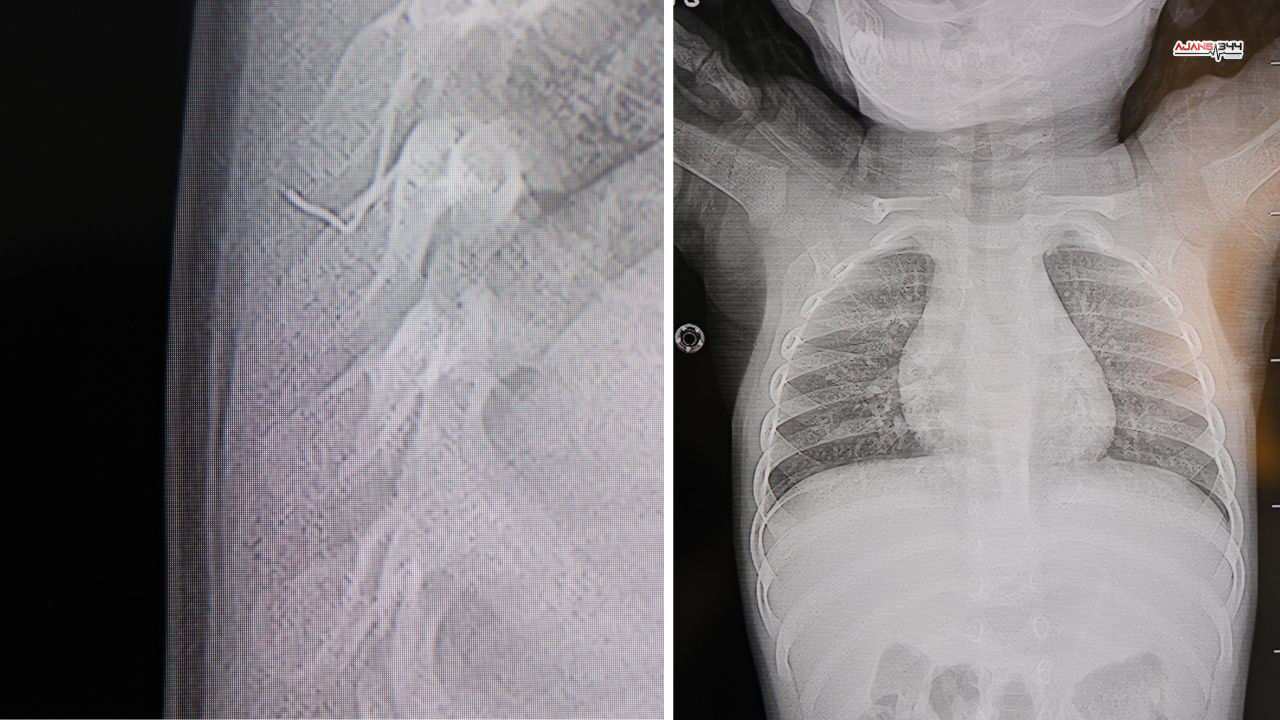

Kahramanmaraş’ta sırt üstü yatırıldığında ağlama ve huzursuzluk yaşayan bir yaşındaki bebekte, yapılan tetkiklerde sırt bölgesinden akciğer zarına doğru ilerleyen metal bir yabancı cisim tespit edildi. Durumun ciddiyeti üzerine bebek, ileri tetkik ve değerlendirme için hastaneye yönlendirildi.

HG Hospital’de yapılan incelemelerde, Prof. Dr. İdris Altun tarafından yabancı cismin cilt altında, omurilik kanalına oldukça yakın bir noktada bulunduğu ve akciğer zarına doğru ilerlediği tespit edildi. Yapılan değerlendirme sonucunda beklemenin ciddi sağlık riskleri doğurabileceği kanaatine varıldı.

Bebek, genel anestezi uygulanmadan, lokal anestezi ve sedasyon eşliğinde ameliyata alındı. Gerçekleştirilen cerrahi müdahalede yabancı cisim tamamen çıkarıldı. Operasyon sırasında çıkarılan cismin, yaklaşık 2 santimetre uzunluğunda, ince zımba teline benzer metal bir tel olduğu belirlendi. Müdahale sonrası herhangi bir komplikasyon gelişmedi.

Operasyonun ardından açıklamalarda bulunan Prof. Dr. İdris Altun, yabancı cismin alınmaması durumunda ciddi sonuçlar doğurabileceğine dikkat çekti. Altun, cismin zamanla enfeksiyona yol açabileceğini, enfeksiyonun omurilik kanalında kalıcı hasarlara neden olma riski taşıdığını belirtti. Ayrıca cismin yana doğru ilerleyerek akciğer zarına ve akciğere batma ihtimalinin bulunduğunu, bunun da ilerleyen süreçte daha ağır klinik tablolara yol açabileceğini ifade etti.